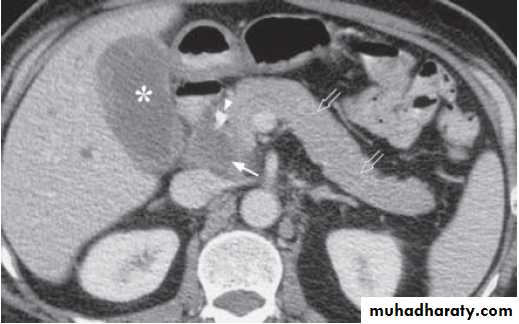

Contrast enhanced axial computed tomography (CT) shows a hypodense tumour in pancreatic head (arrow). The rest of the pancreas appears normal (open arrows). Note the presence of biliary stent (arrowhead) which was inserted to relieve common bile duct obstruction by the tumour. However, the gallbladder (asterisk) remains distended